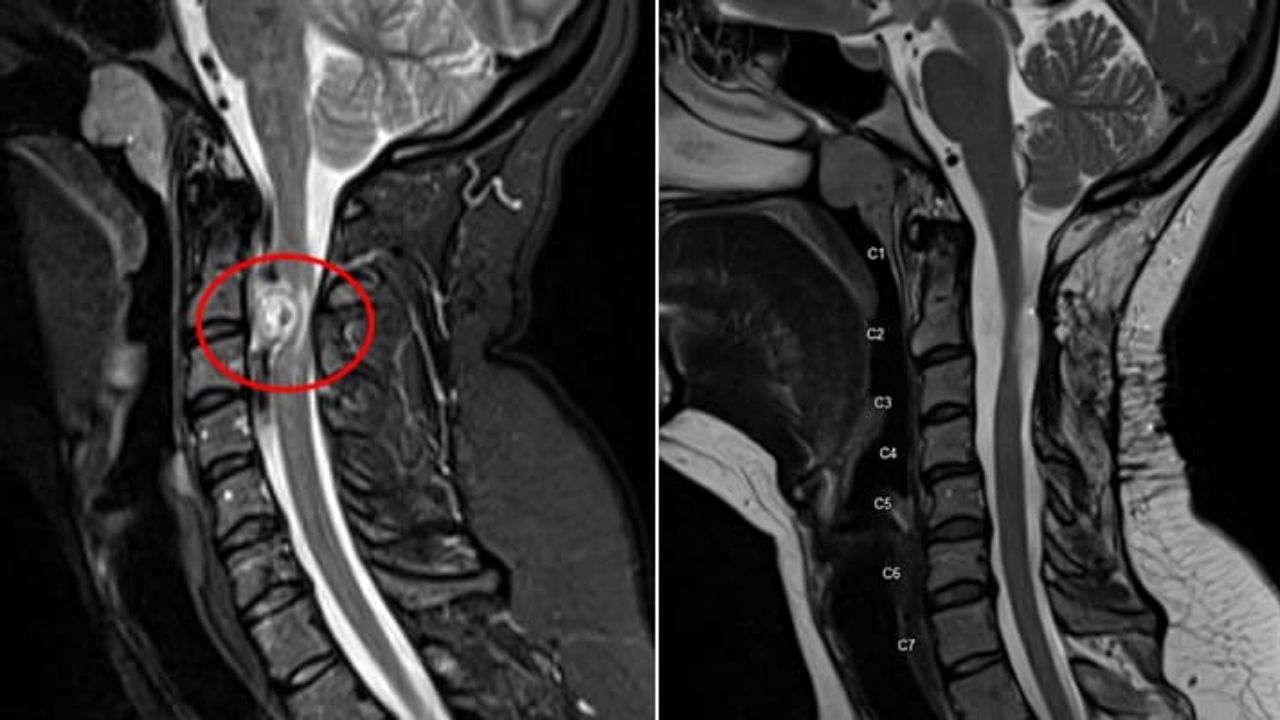

روشهای تشخیص تومور ستون فقرات

ازآنجاییکه علائم این عارضه شباهت زیادی به علائم برخی دیگر از بیماریها دارد. پزشک برای تشخیص به خوبی سابقه پزشکی و خانوادگی شما را بررسی میکند و یک معاینه جسمی و عصبی دقیق انجام میدهد. سپس دستور انجام یک یا چند مورد از آزمایشهای زیر را میدهد:

- روشهای تصویربرداری مانند سی تی اسکن و ام آر آی ستون فقرات